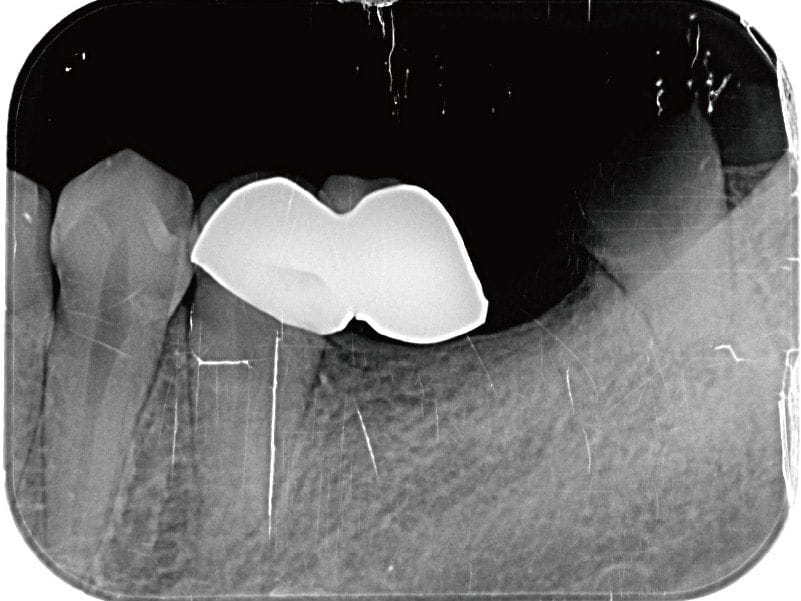

圖示:左下後牙區的假牙和臼齒殘根 圖示:左下後牙區X光片,箭頭處為假牙與臼齒殘根

圖示:假牙拆除前的X光片 圖示:假牙拆除前的X光片